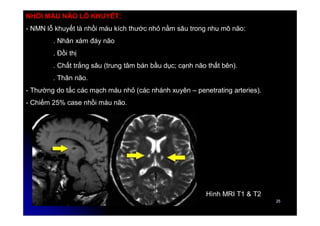

NHỒI MÁU NÃO LỖ KHUYẾT:

- NMN lỗ khuyết là nhồi máu kích thước nhỏ nằm sâu trong nhu mô não:

. Nhân xám đáy não

. Đồi thị

. Chất trắng sâu (trung tâm bán bầu dục; cạnh não thất bên).

. Thân não.

- Thường do tắc các mạch máu nhỏ (các nhánh xuyên – penetrating arteries).

- Chiếm 25% case nhồi máu não.

Hình MRI T1 & T2